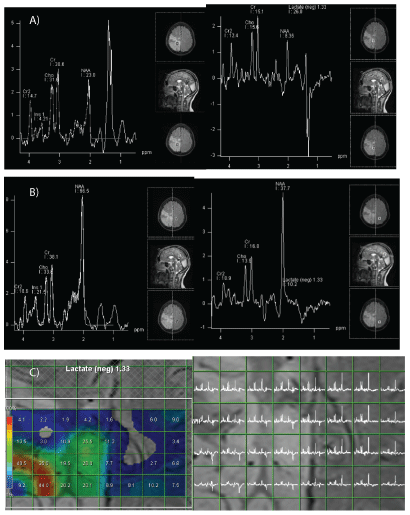

质子磁共振波谱显示,在正常和病理区域以及脑脊液(CSF)中,乳酸比率升高而降低N-病理区域的乙酰天冬氨酸(NAA)比率(图3)。

图3:光谱研究。

A: AMbnormal区域:乳酸浓度在1.33 ppm时升高(红色箭头),在长回声时间的光谱上倒置(绿色箭头)。NAA/肌酸比值降低。

B:形态正常区域:1.33 ppm乳酸双峰,短回声时间谱呈阳性,长回声时间谱呈阴性。

C:光谱制图(长回声时间)显示在病理和形态学正常区域均有乳酸峰。

光谱结果不是MELAS特有的。它可以显示n -乙酰天门冬氨酸(NAA)的减少,这反映了神经元的损失或损伤和乳酸盐的增加,这反映了厌氧代谢。此外,在MRI上可以在正常区域发现乳酸峰,提示并支持线粒体细胞病变理论[1,4]。